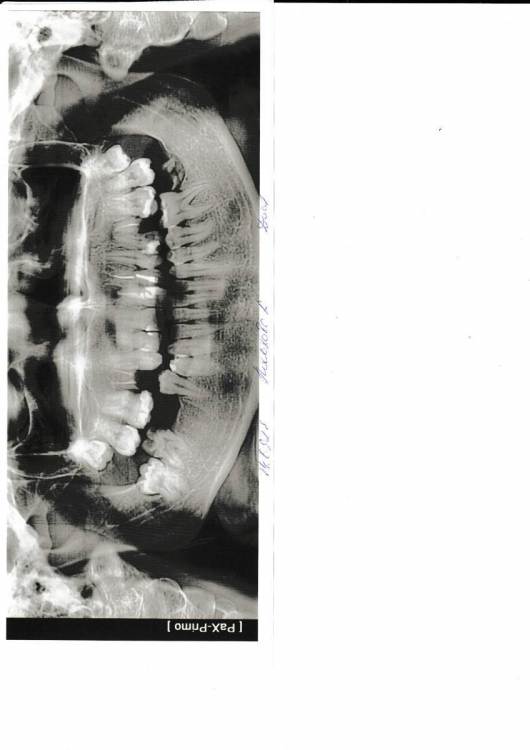

Оксана18 Опубликовано 14 сентября, 2023 Поделиться Опубликовано 14 сентября, 2023 Здравствуйте! Подскажите пожалуйста, однозначно удалять все 4 корня у разрушенных зубов? Они мёртвые? Нужно вставить зубы. И на снимке, справа вверху зуб пятый по счёту, можно ли как то сохранить, если обе боковые стенки разрушены, держится на передней и задней(( Ссылка на комментарий

Женька Опубликовано 14 сентября, 2023 Поделиться Опубликовано 14 сентября, 2023 @Оксана18 здравсвтуйте. Все корни однозначно удалять. 1 час назад, Оксана18 сказал: можно ли как то сохранить как говорится - поздно пить Боржоми Ссылка на комментарий

Doc Опубликовано 15 сентября, 2023 Поделиться Опубликовано 15 сентября, 2023 Лет десять назад бы спросили, можно было бы еще о чем-то поговорить. Ссылка на комментарий